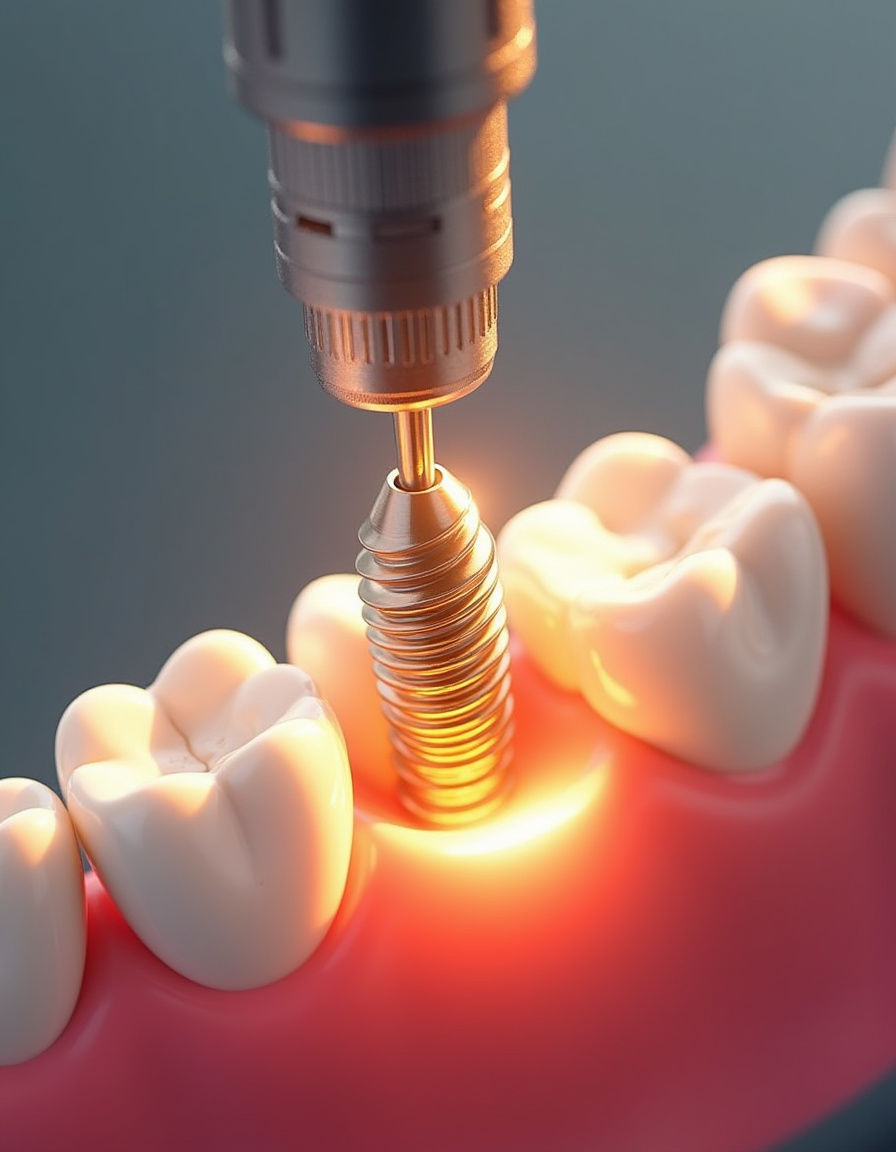

While that titanium post should last forever, the crown (the part that looks like a tooth) will wear down eventually. Most patients need a new one every 10-15 years, costing around $1,000-$2,000.

So over 30 years, you might replace it 2-3 times, totaling $3,000-$6,000. Sounds like a lot until you compare it with replacing entire bridges or dentures multiple times over those same decades.

The Connector Piece

The abutment (the connector between the implant and crown) rarely causes trouble, but occasionally needs replacement at $300-$500. Maybe once or twice in your lifetime, adding roughly $500-$1,000 to your lifetime tally.